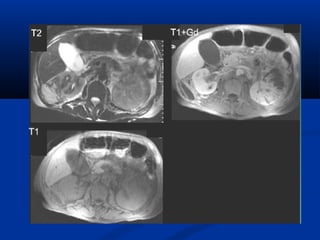

 CT :CT :

 Khảo sát hình thái và chức năngKhảo sát hình thái và chức năng

 KT nhạy nhất để tìm ổ nhiễm trùng : dùngKT nhạy nhất để tìm ổ nhiễm trùng : dùng

dynamic CT, có hình ảnh giữ thuốc cản quang tạidynamic CT, có hình ảnh giữ thuốc cản quang tại

thì muộn.thì muộn.

 Dấu hiệu gián tiếp: đường bờ mờ, dày mạc thận,Dấu hiệu gián tiếp: đường bờ mờ, dày mạc thận,

thâm nhiễm mỡ quanh thận.thâm nhiễm mỡ quanh thận.

Thì nhu mô thì muộn

ThThì muộnì muộn